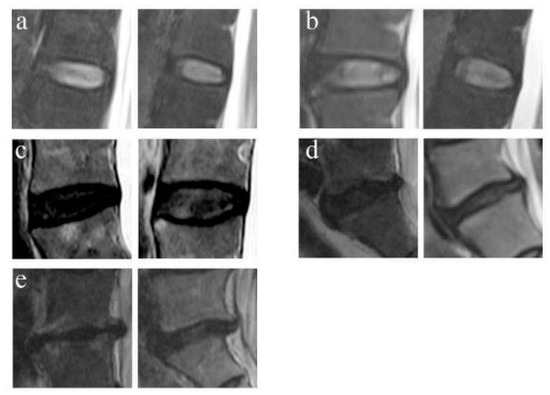

2.4.2. Disc Degeneration Grading

The LDD was classified into 5 grades by using the criterion of Pfirrmann et al. on T2-weighted MRI [9]. Grade 1 corresponds to a normal disc and grade 5 corresponds to a terminal degenerative disc (Figure 2).

Figure 2.

Example of Pfirrmann grades for the LDD. (a) Grade Ⅰ: normal discs. (b) Grade Ⅱ: the mild degeneration discs with structure inhomogeneous with/without horizontal bands. (c) Grade Ⅲ: the moderate degeneration discs with gray structure, can not distinguish the nucleus and annulus, intermediate signal intensity, and normal/slightly decreased disc height. (d) Grade Ⅳ: the severe degeneration disc with gray/black structure, the distinction of nucleus and annulus is lost, intermediate/hypointense signal intensity, and normal/moderately decreased disc height. (e) Grade Ⅴ: End-stage degeneration disc with black structure, the distinction of nucleus and annulus is lost, hypointense signal intensity, and collapsed disc space.